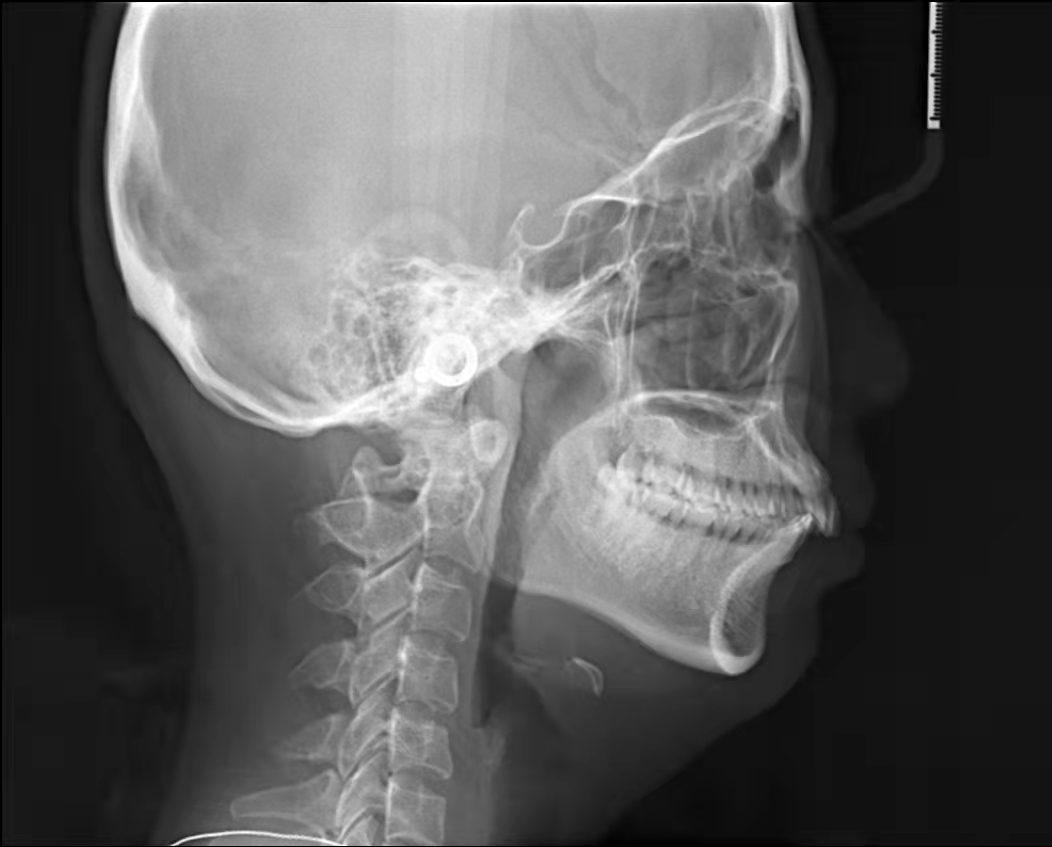

其實(shí)呢牙齒矯正是治病,矯正后變美程度因人而異,但可以確定的是牙齒矯正能使我們外貌有改變

4、齙牙造成面部變形。臉型在人體美中占有重要的位置,臉型的美麗與諧調(diào),是由的牙列來維持的。齙牙咬合受影響,導(dǎo)致面部不協(xié)調(diào),從而加速面部衰竭,由于臉部的骨骼結(jié)構(gòu)也會(huì)影響皺紋形成,齙牙嘴型往前凸,恰好在法令紋位置形成凹陷,法令紋自然會(huì)加深。而且牙槽骨或整個(gè)頜骨因缺乏正常咀嚼氣力的刺激,將會(huì)逐漸蛻變、萎縮,造成下巴的長(zhǎng)度變短,面頰部和四面肌肉松弛,甚至?xí)斐擅娌孔冃巍?/span>